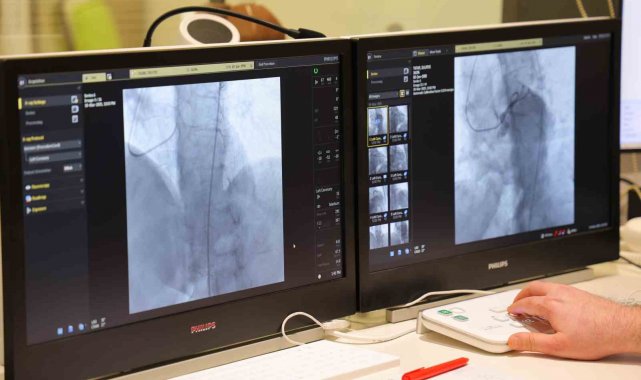

HG Hospital Kalp Merkezi, kardiyoloji ve kalp damar cerrahisi bölümlerinin tam kapasiteyle hizmet vereceğine değinen Prof. Dr. Balcıoğlu, "Bu merkezde anjiyografi ünitemizle kalp ve damar hastalıklarının tanı ve tedavisini yapıyoruz. Koroner damarlar, şah damarları, kol-bacak damarları, aort damarı hastalıkları gibi birçok damar hastalığına yönelik görüntüleme ve tedavi işlemlerini gerçekleştiriyoruz. Ayrıca, doğuştan kalp deliklerinin ve bazı kapak hastalıklarının ameliyatsız yöntemlerle tedavisi, kalp yetmezliği ve ritim bozukluğu tedavisinde kullanılan kalp pillerinin yerleştirilmesi işlemlerini de anjiyografi laboratuvarımızda uyguluyoruz. Kalp Damar Cerrahisi kliniğimiz de kapalı yani minimal invaziv ya da endoskopik yöntemlerle göğüs kafesinde büyük kesilere ihtiyaç olmadan koroner bypass cerrahisi ve kalp kapağı değişim operasyonlarını yapabilmektedir. HG Hospital kalp merkezi, ileri düzey anjiyografi ünitesi, koroner ve kalp damar cerrahisi yoğun bakım üniteleri ve kalp damar cerrahisi ameliyathanesiyle hizmet verecek. Merkezimizde, üniversite hastanemizde yıllardır gerçekleştirdiğimiz işlemleri burada sürdürmemize imkan tanıyacak şekilde donatıldı. Kahramanmaraş'ta vatandaşlarımızın ileri düzey kalp sağlığı hizmetlerine ulaşmasını sağlayacağız" ifadelerini kullandı.